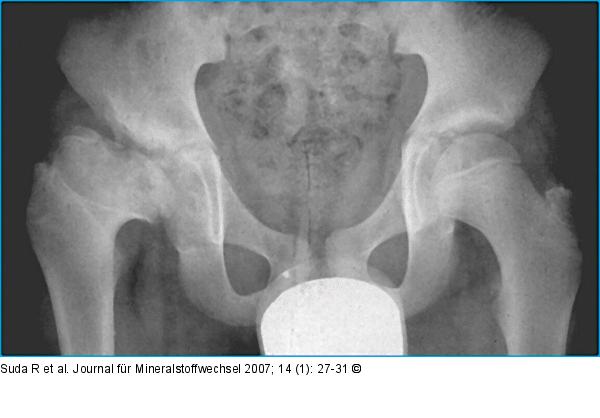

Abbildung 5: Morbus Perthes Morbus Perthes rechts im Endstadium mit Defektheilung: Der Femurkopf zeigt eine asphärische Deformierung im Sinne einer Coxa parva et breva. |

Morbus Perthes rechts im Endstadium mit Defektheilung: Der Femurkopf zeigt eine asphärische Deformierung im Sinne einer Coxa parva et breva. |